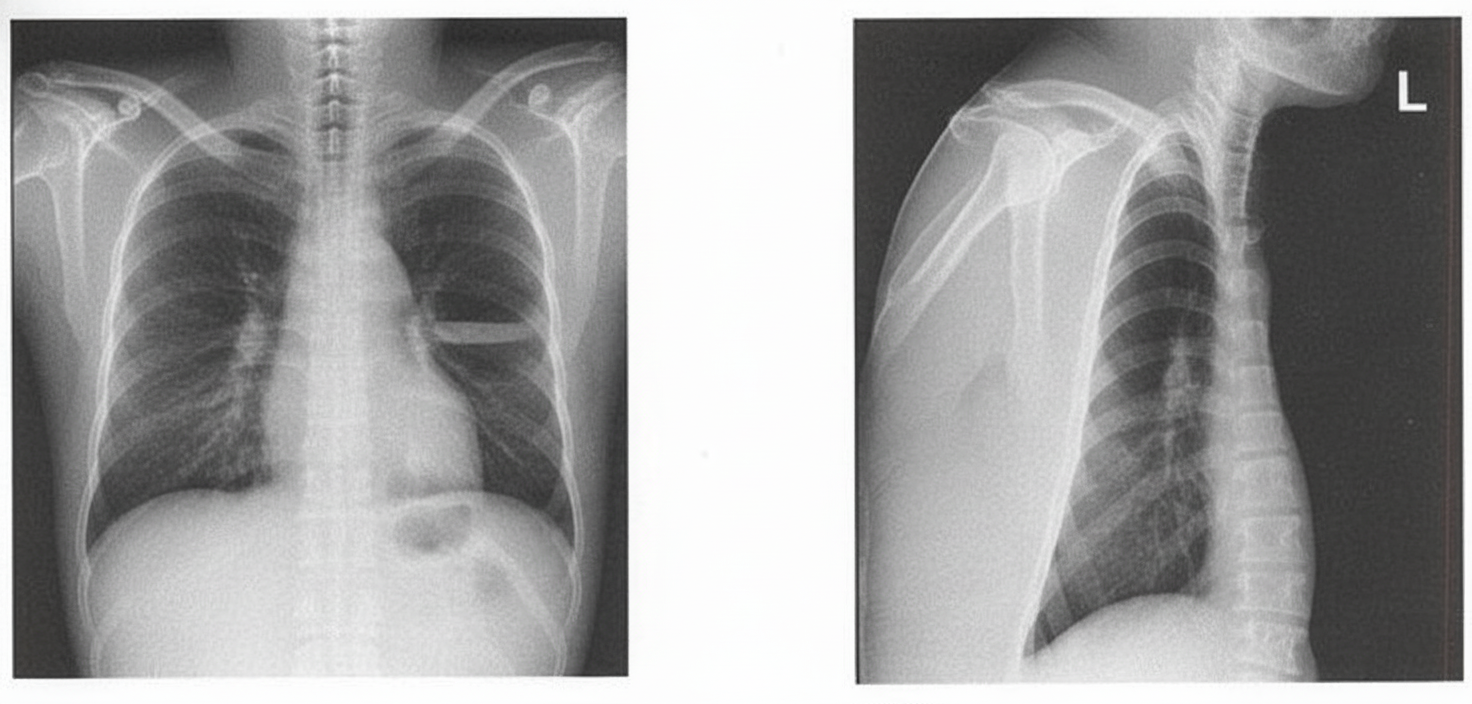

Question 3: A patient presents with foul-smelling sputum along with breathlessness and fever. Using the X-ray below, identify the diagnosis.

- D. Lung Abscess (Correct Answer)

Explanation: ***Lung Abscess*** - The combination of **foul-smelling sputum** (indicating anaerobic bacterial infection), breathlessness, and fever is **pathognomonic for lung abscess** - The X-ray demonstrates a **characteristic air-fluid level** within the lung parenchyma, which is the hallmark radiographic finding of a cavitating lung abscess - When a lung abscess ruptures into a bronchus, it produces the typical **foul-smelling, purulent sputum** described in this case - Common causes include aspiration pneumonia, particularly in patients with risk factors like alcoholism, poor dental hygiene, or altered consciousness *Pleural Effusion* - While pleural effusion can present with breathlessness and fever, it would **not produce foul-smelling sputum** - A simple pleural effusion appears as **blunting of the costophrenic angle** or a **meniscus sign**, not an air-fluid level within the lung field - An empyema (infected pleural effusion) with bronchopleural fistula could theoretically show an air-fluid level, but this would be in the **pleural space**, not within the lung parenchyma, and is much less common than lung abscess *Pneumothorax* - Pneumothorax shows **air in the pleural space** with visible lung edge and absent lung markings peripherally - There would be **no fluid component** and no foul-smelling sputum - The air-fluid level seen here indicates a cavitary lesion, not a pneumothorax *Pericardial Effusion* - Pericardial effusion presents with an **enlarged, globular cardiac silhouette** ("water bottle heart") - It would **not cause respiratory symptoms** like foul-smelling sputum or the radiographic findings shown - The pathology is clearly in the **lung field**, not around the heart